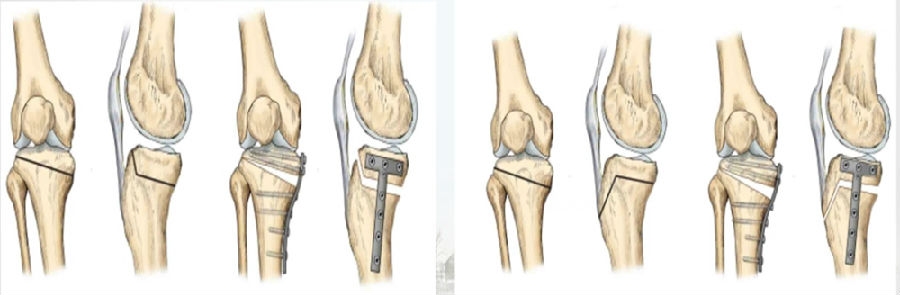

1)外侧闭合楔形截骨(CWHTO)

去除外侧一个楔形骨块,将下肢力线外翻来降低内侧间室的压力。

外侧闭合楔形截骨

优点:截骨端加压闭合,无需植骨。

缺点:造成下肢短缩,矫正度数有限,需行腓骨截骨;容易损伤腓总神经,甚至可能出现筋膜室综合征。

2)内侧开放楔形截骨(OWHTO)

胫骨近端内侧楔形截骨,逐渐撑开截骨端,改善力线。

内侧开放楔形截骨

优点:更精确,矫正角度较大,无需腓骨截骨。

缺点:截骨端愈合时间长;撑开角度大,需要植骨促进愈合,髌骨高度影响。

3Hybrid CWHTO

矫正角度过大,可采用Hybrid CWHTO,改变截骨合页点,有效避免CWHTOOWHTO的缺点。

混合截骨